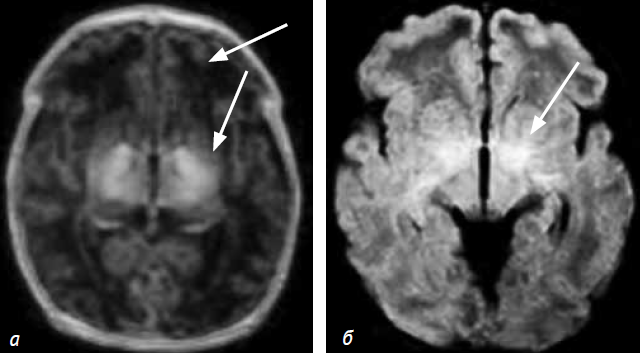

При краниальной сонографии выявлены постгипоксические изменения: симметричное усиление эхосигнала от базальных ядер и зрительных бугров с первых суток жизни (рис. 1).

Рис. 1. Пациент C. Краниальная сонография (первые сутки жизни), парасагиттальный (а) и фронтальный (б) срезы. Стрелками отмечены участки усиления эхосигналов от зрительного бугра и базальных ядер

Краниальная сонография, выполненная в день поступления и в динамике, выявила симметричное изменение эхосигнала в области зрительных бугров.

Результаты обследования представленных пациентов выявили клинические и нейровизуализационные паттерны повреждения головного мозга, характерные для ГИЭ у доношенных новорожденных, что было отмечено и другими исследователями [14]. Основной нейровизуализационный паттерн постгипоксических изменений головного мозга представлен повреждением зрительных бугров и базальных ганглиев. Это связано с тем, что эти области имеют высокую метаболическую активность и часто повреждаются [3]. Подобные изменения характеризуются усилением (пациенты С. и М.) эхосигнала от базальных ганглиев и зрительных бугров в остром периоде ГИЭ, что подтверждается данными МРТ. Характерные МРТ-паттерны ГИЭ у доношенных новорожденных диагностированы на 14–16-й день жизни, которые характеризовались изменением сигнала в течение 6 недель (контрольная МРТ пациента С.). При этом были выявлены изменения в гиппокампах (пациент С.). Полученные данные также были подтверждены другими исследователями [4, 10, 12]. Следует отметить, что у пациентов изменения выявлялись в зонах, прилегающих к КСТ, в виде усиления сигнала от перивентрикулярных зон (пациент М.) и наличия ликворных кист у переднего отдела внутренней капсулы (пациент С.) без признаков повреждения тракта. Предполагается возможность изменений микроструктуры проводящих путей (и прежде всего КСТ) в случаях повреждения базальных ганглиев и зрительных бугров у доношенных новорожденных с ГИЭ [2, 18]. В нашем исследовании (см. табл. 1) выявленное изменение КФА КСТ при повреждении базальных ганглиев и зрительных бугров может служить подтверждением предположения о нарушении микроструктур проводящих трактов у новорожденных детей с ГИЭ. Вторая возможная причина изменения КФА КСТ у новорожденных детей с постгипоксическим повреждением зрительных бугров и базальных ганглиев может быть связана с нарушением/задержкой миелинизации трактов у таких новорожденных, что нашло подтверждение в работах других исследователей [19]. Однако интерпретация данных трактограмм, результатов данных фракционной анизотропии осложняется отсутствием «норм» для новорожденных различного гестационного возраста. Трактография в настоящее время представляет предмет научных исследований головного мозга новорожденных детей и является наиболее перспективным методом изучения проводящих путей in vivo [13].